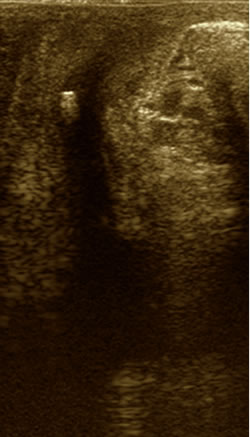

УЗИ

промежности |

|